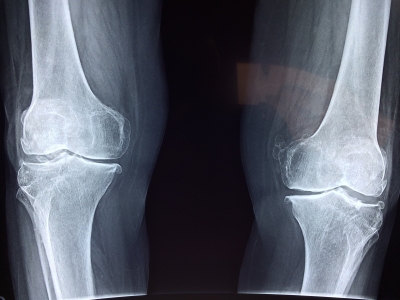

The surgery, named high tibial osteotomy, is a knee surgery aimed at younger patients in the earlier stages of knee osteoarthritis, according to the study published in CMAJ (Canadian Medical Association Journal).

Knee osteoarthritis is a common cause of pain and disability and puts tremendous burden on health care systems. Total knee replacement is frequently performed on older patients with end-stage disease and limited mobility.

Of the patients in this study getting high tibial osteotomy (643 knees in 556 patients), 95 per cent did not need a total knee replacement within 5 years, and 79 per cent did not get a total knee replacement within 10 years.

Even in patients traditionally not considered ideal candidates for high tibial osteotomy (e.g., women and patients with later-stage disease), about 70 per cent did not get a knee replacement within 10 years.

The procedure is particularly suitable for people who are younger, have less severe joint damage and who may be more physically active.